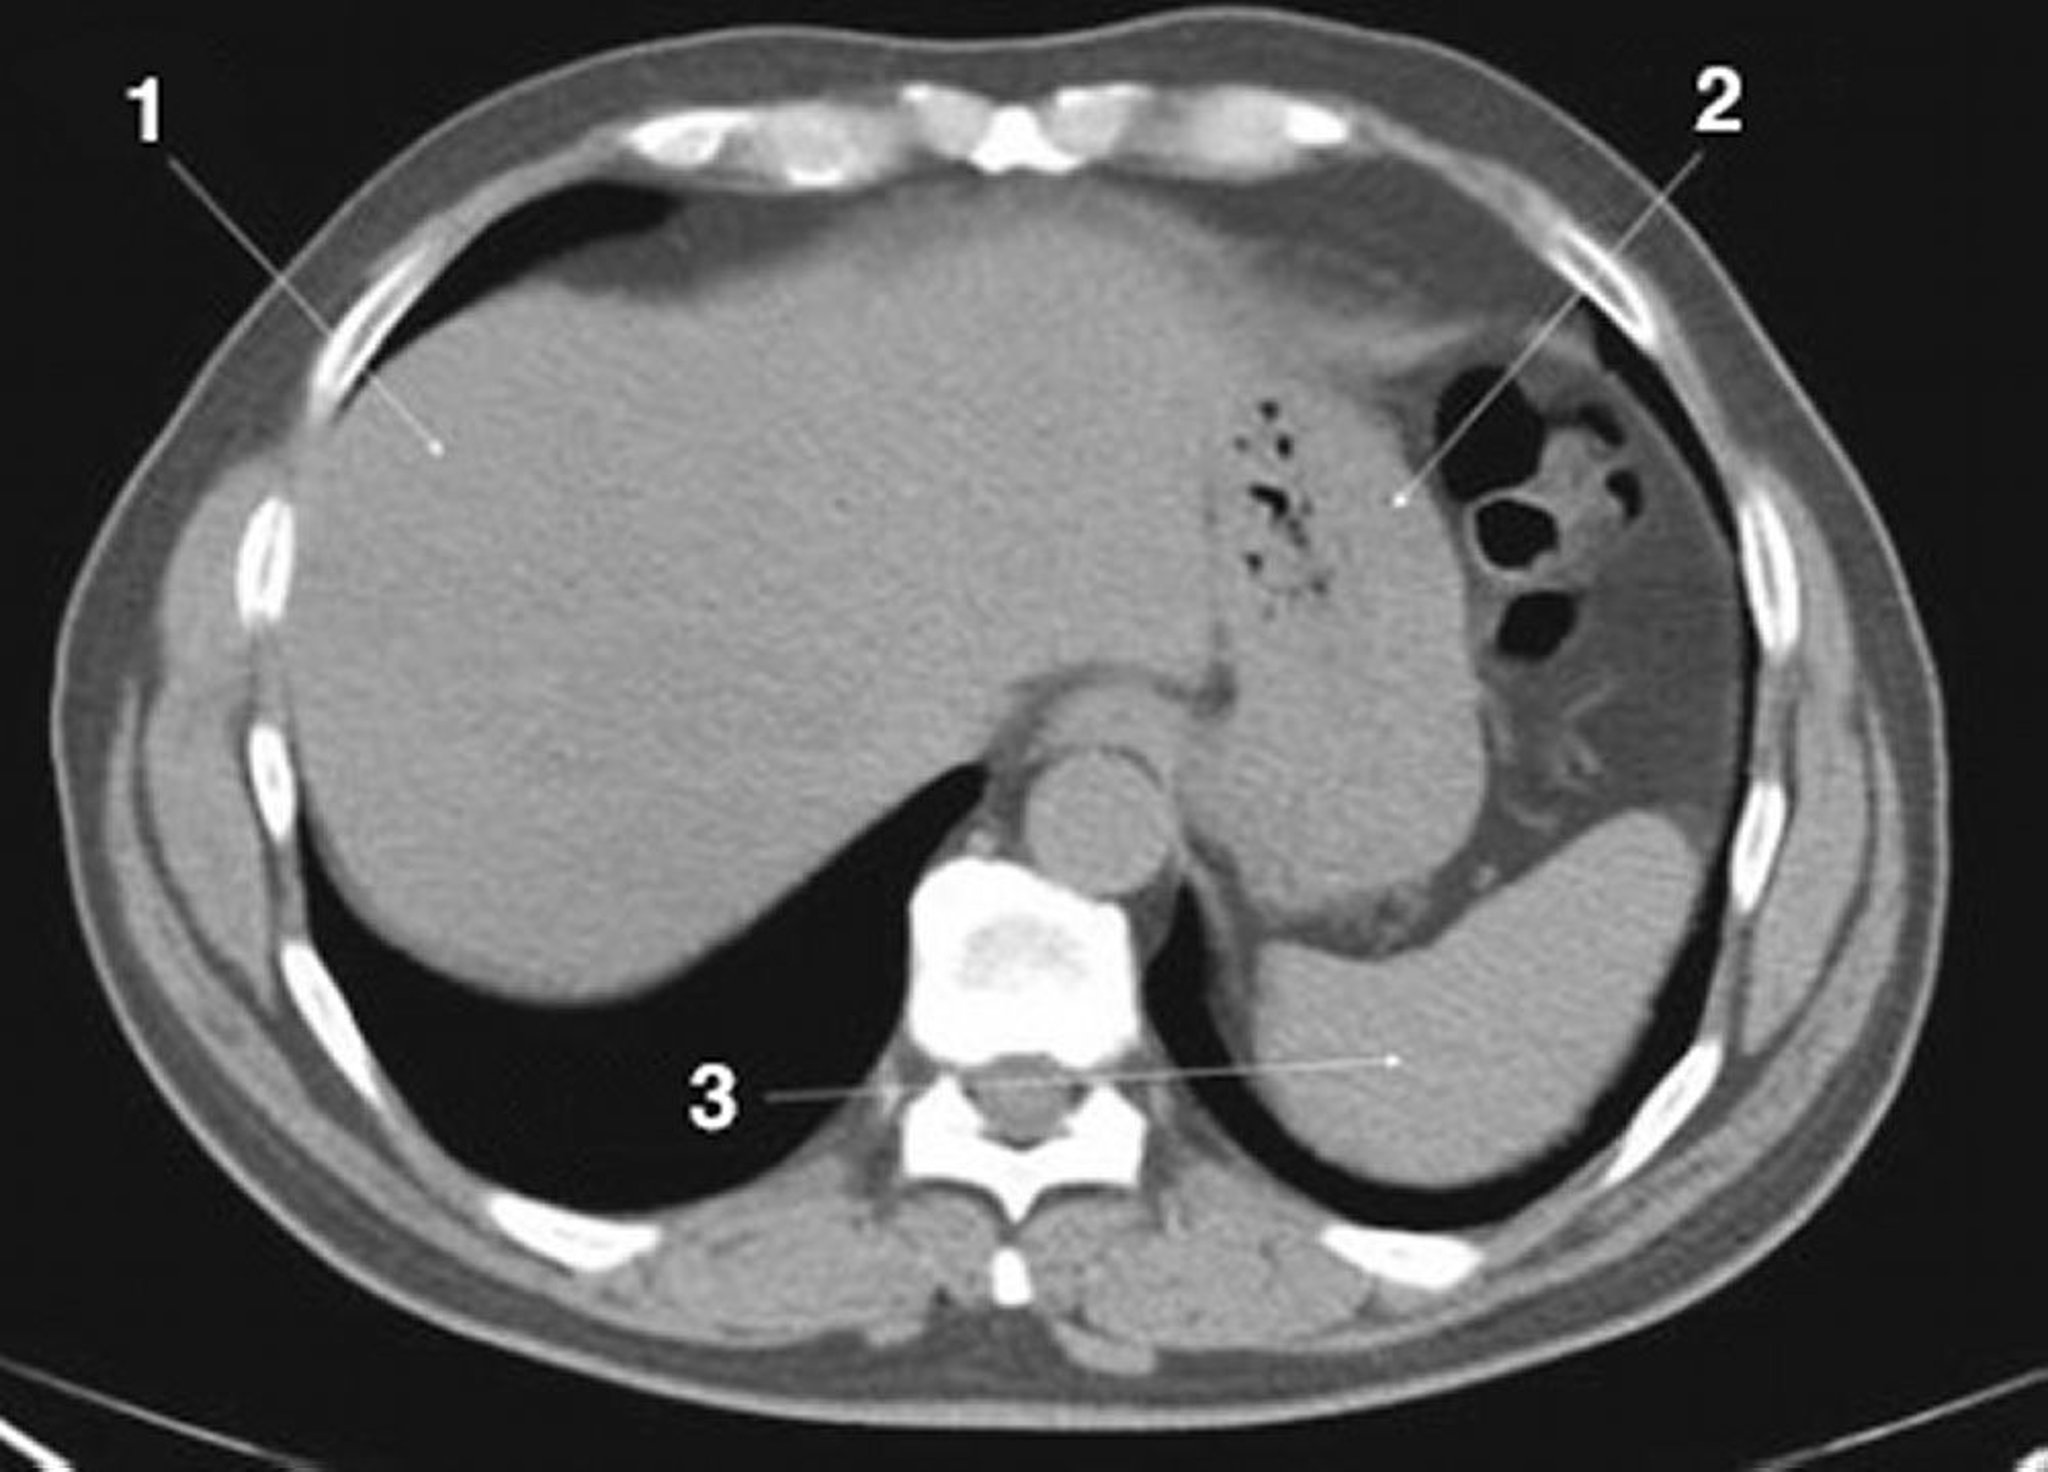

Noncontrast CT Scan of the Abdomen and Pelvis Showing Normal Anatomy (Slide 3)

1 = liver; 2 = stomach; 3 = spleen.